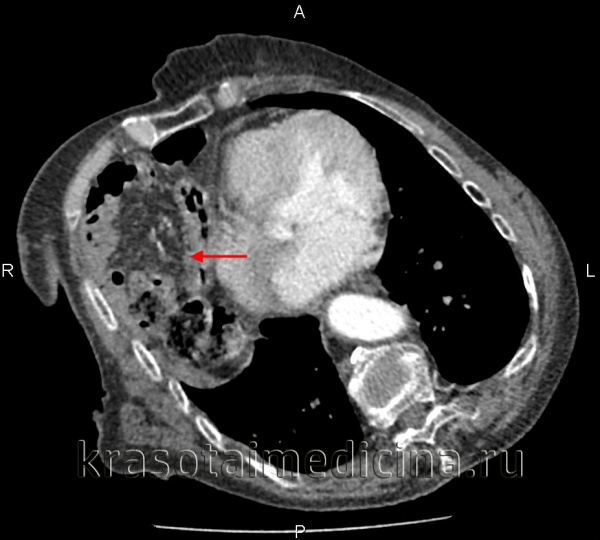

КТ органов грудной клетки/брюшной полости. Травматический дефект в передних отделах диафрагмы справа с эвентрацией кишечника, сальника, кровеносных сосудов в грудную полость